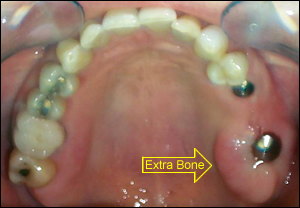

Fig 3: The two dental implants are in place. The posterior implant was strategically placed at the junction of the boney septum of the maxillary sinus. See Fig 8. The naturally occurring bulk of bone seen on the palatal side of the posterior implant further stabilized this implant.